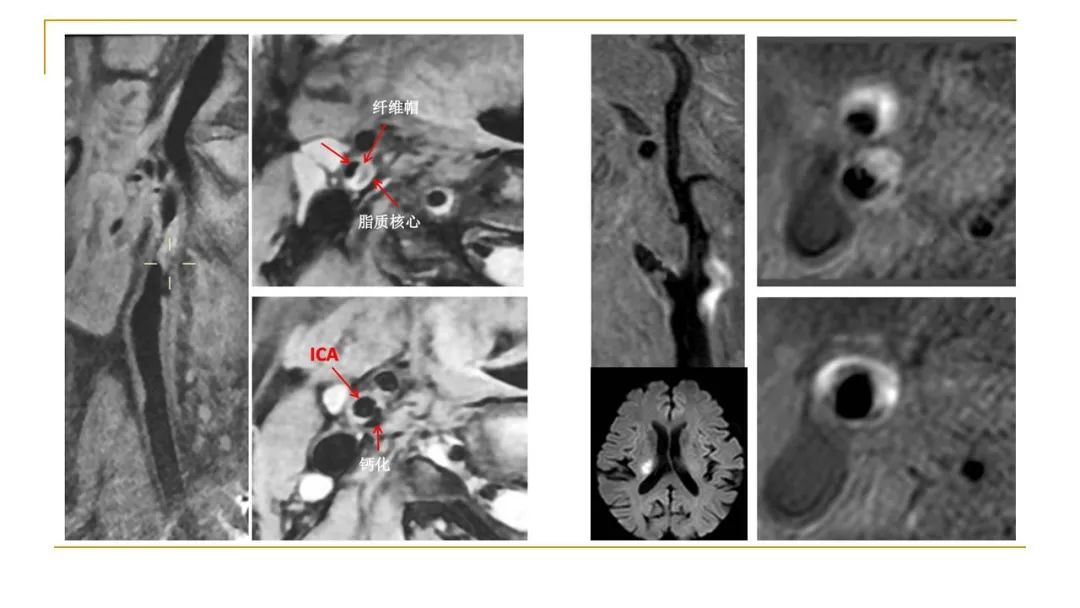

颅颈动脉MR高分辨血管壁成像

【专题三】临床应用